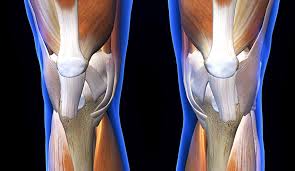

For optimal joint function, it is important to beat inflammation wherever possibleinflammation is the primary source of collagen and, by extension, cartilage breakdown. Vitamin k is essential for bone and joint health. See full list on arrowheadhealth.com Additionally, because collagen is a protein, the protein content of legumes is helpful in replenishing the collagen necessary to rebuild cartilage. And, as if all of that werent enough, legumes also have high levels of lysine, an amino acid that is critical to the cartilage regeneration. See full list on arrowheadhealth.com As we grow up, we tend to forget. Vitamin c is found in onions, peppers, potatoes, lettuce, oranges, tangerines, grapes, citrus fruits, blackberries, as well as many others including and their juices. They help in the production of collagen, which is important for the regeneration of the knee cartilage. But, to amplify the effectiveness of other treatments, maximize your quality of life and avoid dangerous interventions like complicated surgeries, being conscious of the foods you eat and making purposeful, healthy choices to promote cartilage regeneration is key. Oranges are an obvious choice in terms of getting vitamin c to promote the building of collagen as well as to promote cellular healing, which by extension is helpful in cartilage regeneration and protection. Cartilage is an important connective tissue found throughout our bodies. You will be happy to know that collagen is also important for maintaining youthful skin.

When used as part of a larger, comprehensive treatment plan, nutrition can be a great way to confront some of the symptoms of osteoarthritis and other disorders that result from degeneration of cartilage. Find knee cartilage injury help here. Find knee cartilage injury help here. Collagen, which is a protein that your body needs vitamin c to make, is one of the primary components of cartilage. Cartilage is an important connective tissue found throughout our bodies. As we grow up, we tend to forget. And, as if all of that werent enough, legumes also have high levels of lysine, an amino acid that is critical to the cartilage regeneration. Oranges have a good amount of vitamin c, which goes a long way in promoting the building up of collagen to promote cellular healing. Clinically proven to help grow joint cartilage in 2 weeks. Dark green and leafy vegetables. See full list on arrowheadhealth.com Foods rich in vitamin c for regeneration of cartilage of the hip and knee; But, to amplify the effectiveness of other treatments, maximize your quality of life and avoid dangerous interventions like complicated surgeries, being conscious of the foods you eat and making purposeful, healthy choices to promote cartilage regeneration is key.

They help in the production of collagen, which is important for the regeneration of the knee cartilage.